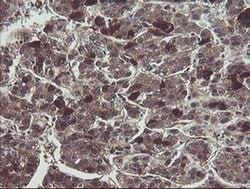

TSC22D1 Monoclonal Antibody (OTI1A5), Invitrogen™

TSC22 domain family protein, or TSC22, is a transcription factor that belongs to the large family of early response genes. This transcriptional repressor is known to act on the C-type natriuretic peptide (CNP) promoter. TSC22 belongs to the TSC-22/Dip/Bun family and is an intracellular protein that may be found in the cytoplasm or nucleus. This transcription factor is known to regulate cell growth, differentiation and cell death and is involved in modulating the transcriptional activity of Smad3 and Smad4. This protein is ubiquitously expressed in most tissues and widely in both fetal and adult tissues. It is generally expressed in aortic endothelial cells, and induced by cytokines, including TGFB. These proteins may be possible therapeutic targets of leukemia and prostate cancer.

| Immunohistochemistry (Paraffin), Western Blot | |